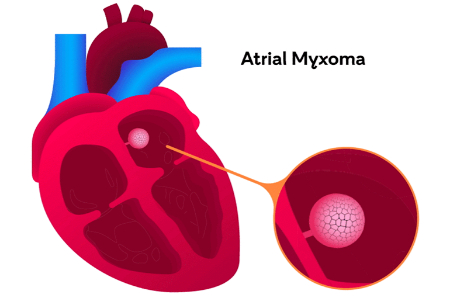

میگزوم قلبی یک تومور است که بر قلب تاثیر میگذارد. این شایعترین تومور غیرسرطانی اولیه قلب است. اندازه میگزومها متغیر است. برخی از آنها به اندازه 1 سانتیمتر قطر دارند، در حالی که برخی دیگر میتوانند تا 15 سانتیمتر رشد کنند. حدود 74% از تمام میگزومها در دهلیز چپ، که اتاق بالایی سمت چپ قلب است، ایجاد میشوند. حدود 18% در دهلیز راست شکل میگیرند. بیشتر میگزومها به عنوان میگزومهای دهلیزی شناخته میشوند زیرا در اتاقهای بالایی قلب ایجاد میشوند. باقیمانده (8%) در بطنها (اتاقهای پایین قلب) شکل میگیرند.

میگزومها معمولاً از سپتوم دهلیزی رشد میکنند. این دیواره عضلانی است که دهلیز چپ و دهلیز راست را از هم جدا میکند. آنها معمولاً با یک پدیکل (پایهای که اجازه میدهد میگزوم حرکت کند) به سپتوم متصل میشوند. تومور میتواند حرکت کرده و گاهی به یکی از دریچههای قلب بیفتد و باعث مشکلات در جریان خون شود.